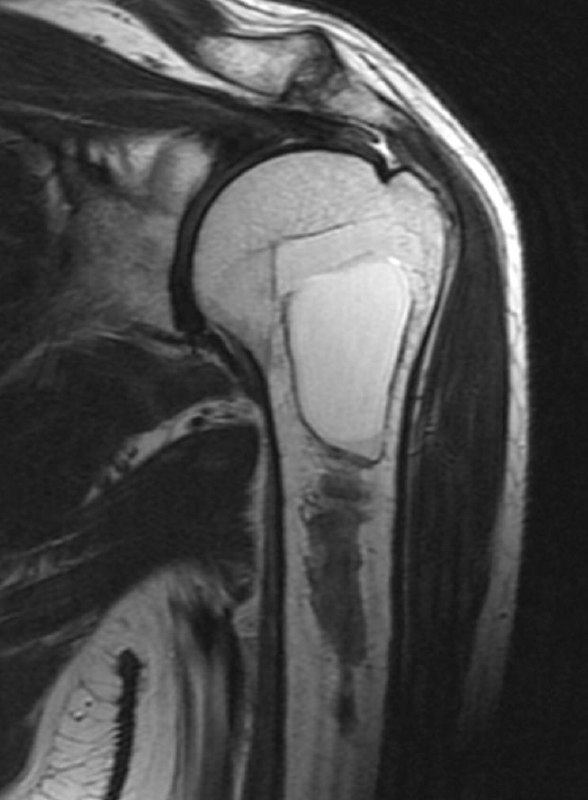

показательный случай острого (хорошо, свежего!) разрыва сухожилия длинной головки бицепса плеча, с приличным диастазом. стрелками указаны края дистального и проксимального фрагментов сухожилия. На последнем снимке - пустая межбугорковая борозда